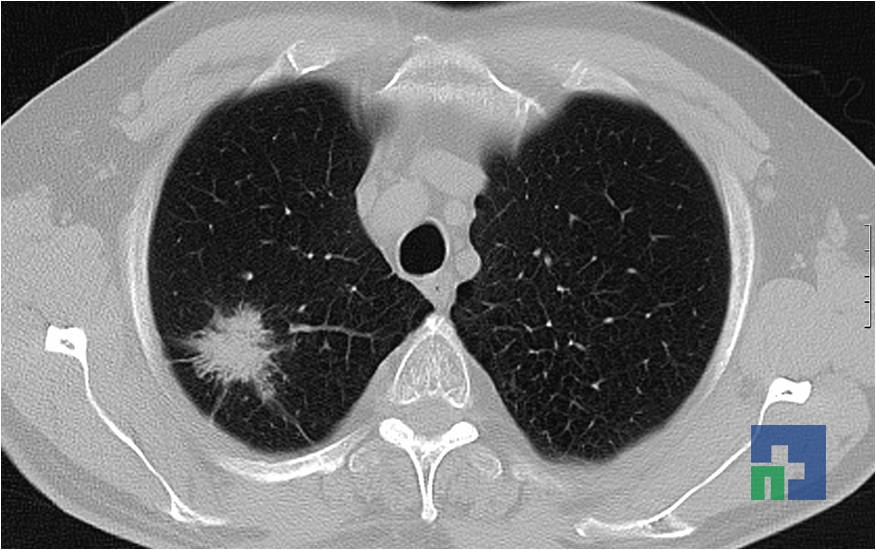

- Tumorilor cerebrale

- Tumorilor cerebrale: